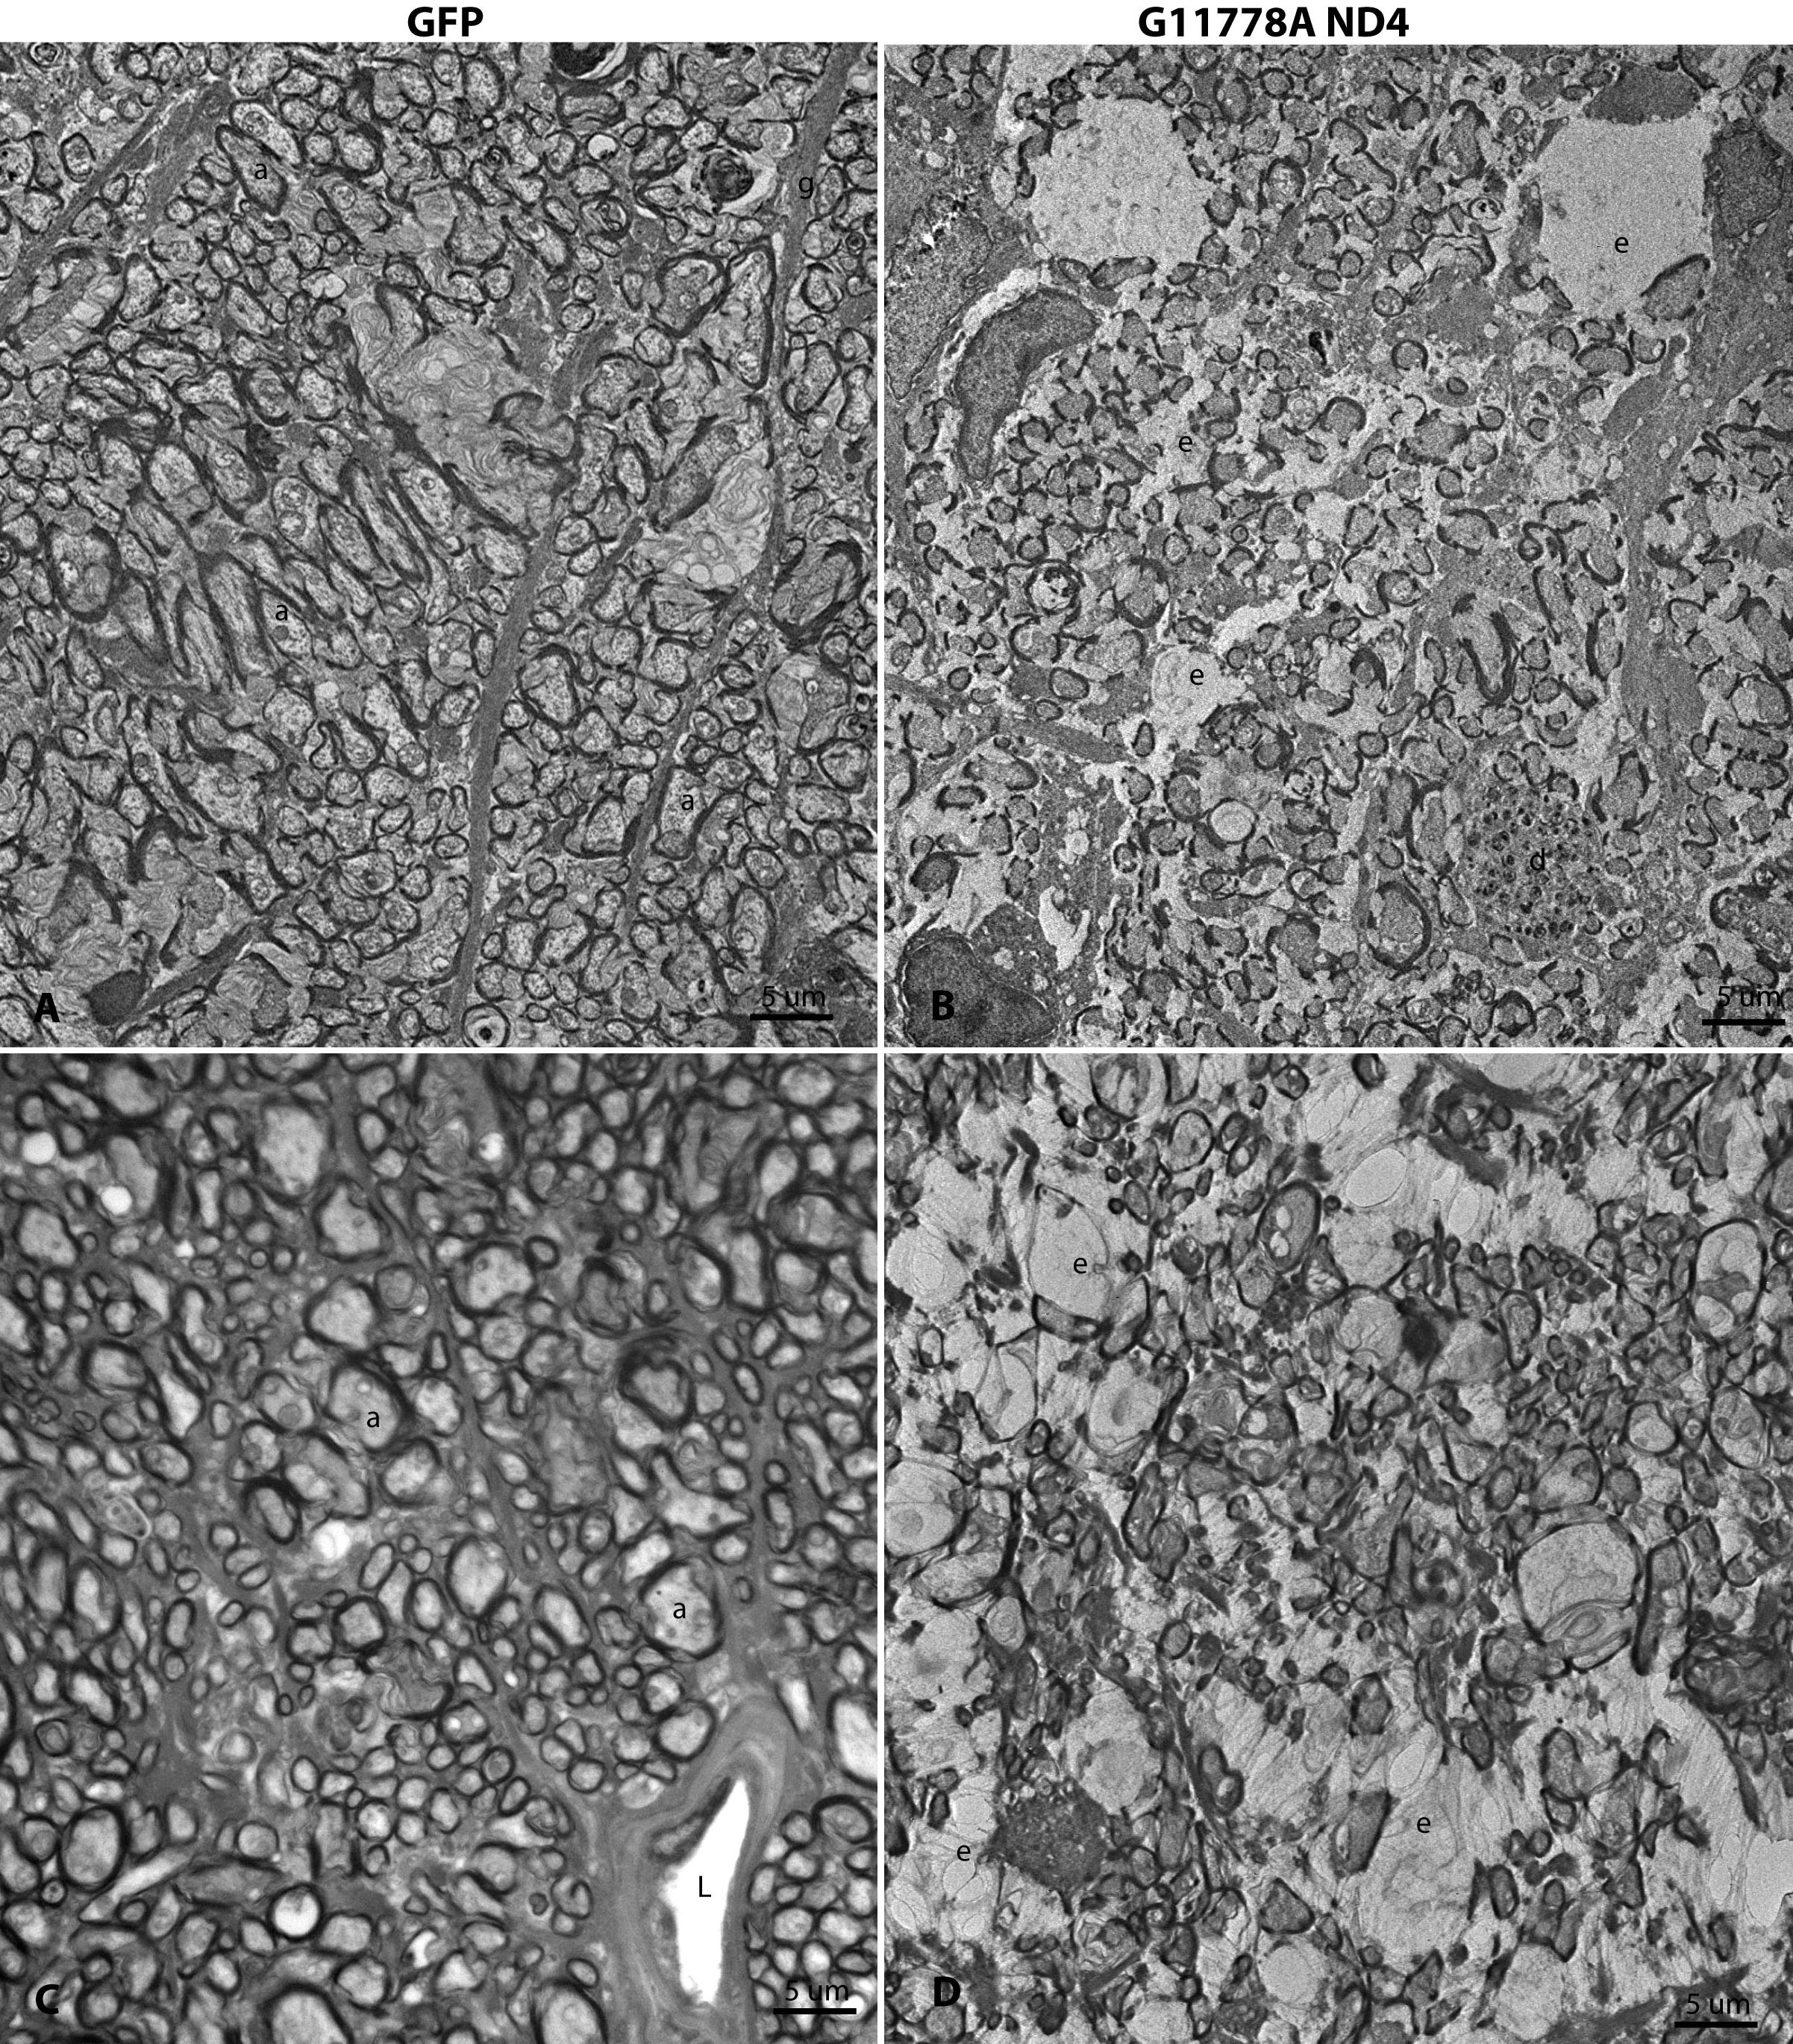

Figure 8. Ultrastructure of optic

nerve axonal loss. A: One year after injection of scAAV-GFP,

transmission electron micrographs disclosed optic nerve axons

(a) of various sizes enveloped by myelin sheaths. Astroglial

cell processes (g) coursed between fibers of the optic nerve. B:

In this same animal, the opposite eye injected with the MTS

scAAV mutant ND4 had a marked decrease in axonal

density. Many empty spaces (e) were present where axons were

apparently lost in these atrophic optic nerves and degenerating

axonal profiles were evident (d). C: In a different

animal, the optic nerve of the control eye injected with scAAV-GFP

had normal axons (a) with the only empty space the lumen of a

blood vessel (L). D: In this animal, the opposite eye

injected with the MTS scAAV mutant ND4 had a marked decrease in

axonal density. Many empty spaces (e) were present where axons

were lost. a=optic nerve axon, e=empty space, g=astroglial

process, d=degenerating axon, L=lumen.